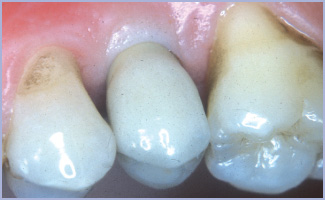

Il tappo di guarigione in zona 45 è rimosso per la presa dell’impronta. Si evidenzia che la gengiva aderente dei denti adiacenti all’impianto non supera il millimetro e mezzo, mentre intorno al tappo l’altezza degli stessi è stata incrementata fino a 4 mm (figg. 1–2). In particolare il tunnel mucoso è ispessito grazie alla modalità chirurgica monofasica. L’integrazione del restauro protesico nei tessuti molli circostanti è ottima (figg. 3-6).